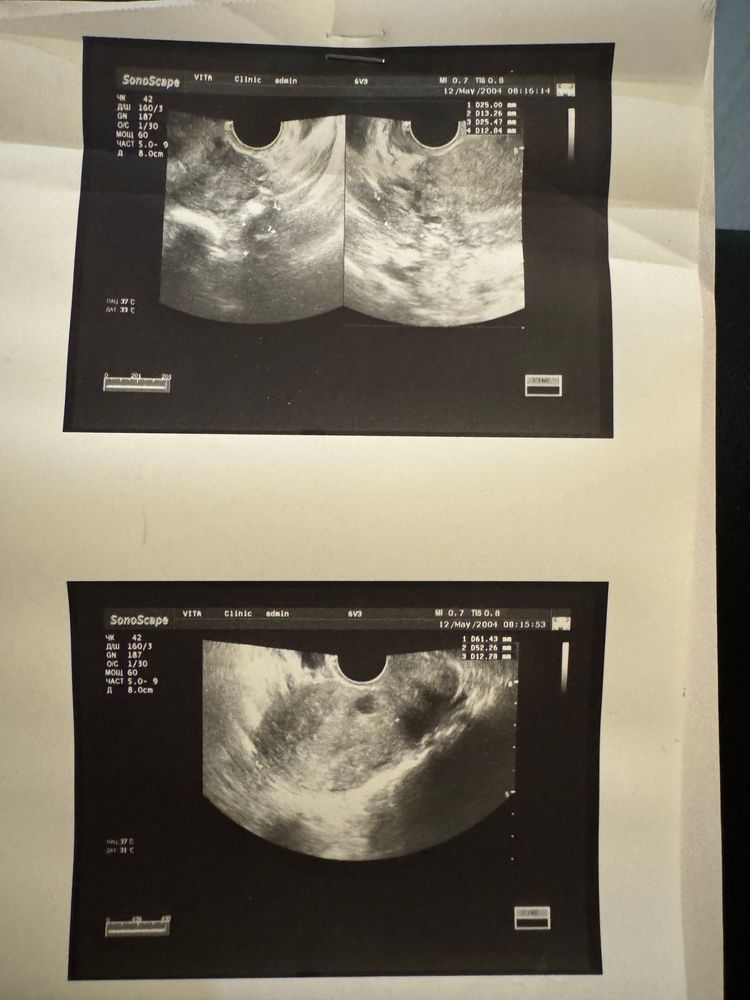

Дарья, по узи доменантоного нет фолликула и признаков прошедшей овуляции тоже не описано

Дарья, ну если нет доминантного фотика и нет желтого тела , то значит ановуляторный цикл, без овуляции , возможно задержка будет, пришлите узи что на второй странице? Просто по правому и левому яичнику максимум фолликулы у вас 5 и 6 миллиметров , а для овуляции это минимум 19 миллиметров должно дать

Мария , там нет продолжения все вот на одном листе и снимок прикреплю

Дарья, по описанию у вас нет доминантного и нет признаков прошедшей овуляции, ждите новый цикл с задержкой скорее всего

Дарья, Вы потом отпишитесь когда цикл начнется, сколько по итогу дней задержка будет, по узи я предполагаю, что до 14 дней возможна, а там Бог знает, может и чудо. Для души хгч сдайте, чтобы не гадать, он и дешевле тестов выйдет и достовернее